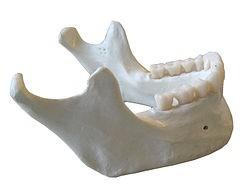

 1. A 36 year old female with a multilocular radiolucency of the left body of mandible. Histology shows islands of epithelium composed of loosely cohesive cells centrally with peripheral palisading and reverse polarity

Ameloblastoma

 Most common odontogenic tumour (exc odontoma which is hamartomatous)

 Wide age range

 Benign but locally aggressive

 Classical histological appearances

Peripheral palisading

Reverse polarity

Central stellate reticulum-like cells